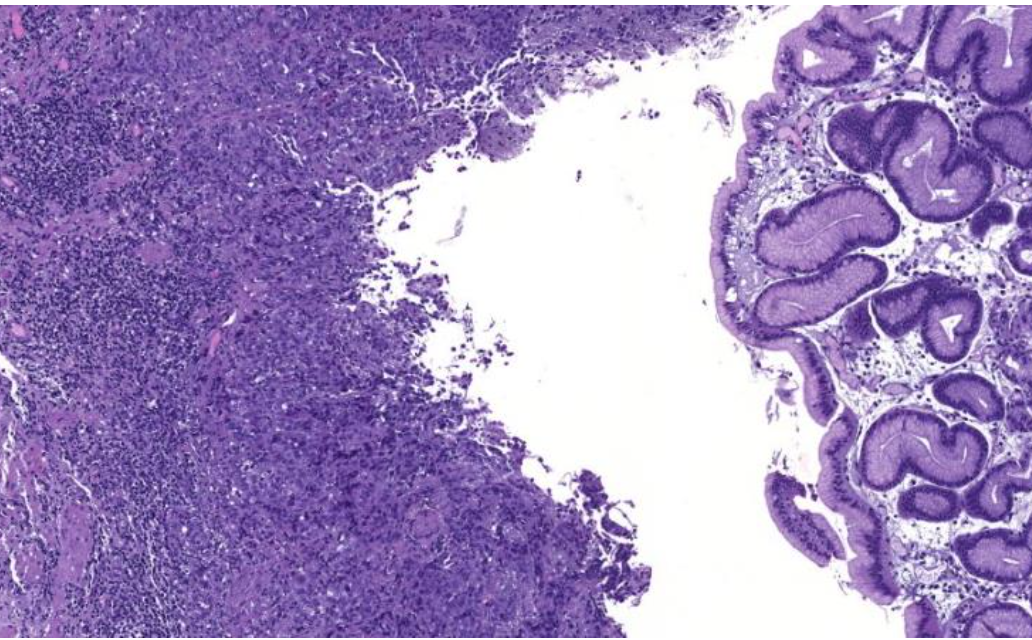

Diagnose?

Dickdarmadenome

Kolorektales Adenokarzinom